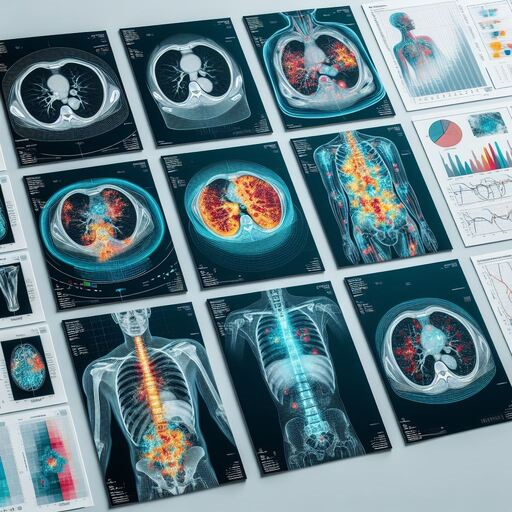

DeepInfinity.AI specializes in using advanced Generative AI and ML technologies to transform healthcare diagnostics and patient care. Our platform applies generative AI models for deep and accurate analysis of medical data, offering a range of predictive and diagnostic tools. These tools are designed to support healthcare professionals in making faster, more accurate diagnoses, thereby enhancing the overall quality of patient care. DeepInfinity.AI uses the advanced Generative AI technology to help Doctors, Hospitals and Diagnostic Centers & Labs etc.